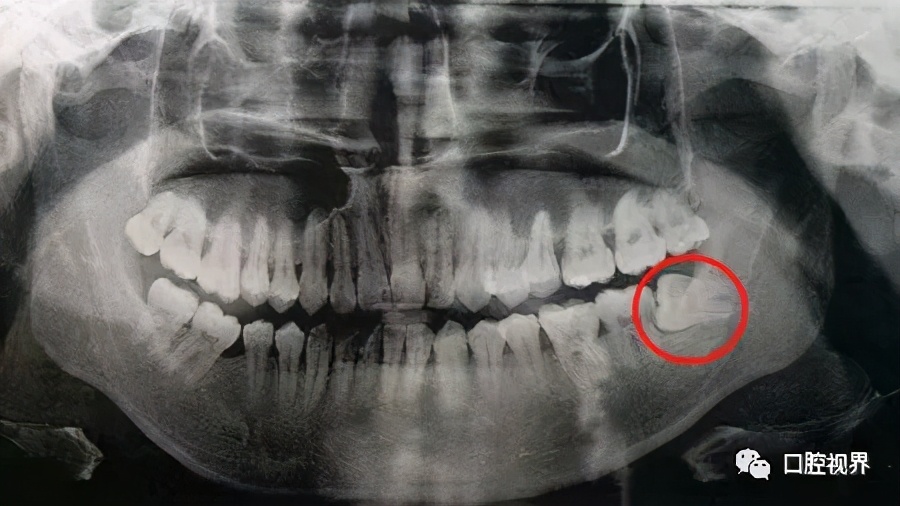

有些拔除智齿较晚的小伙伴(25周岁以上),由于智齿长期依靠在旁边的第二磨牙处,使其严重受损。

导致第二磨牙的牙槽也严重吸收。

这种情况下是可以考虑进行位点保存手术的。如图——